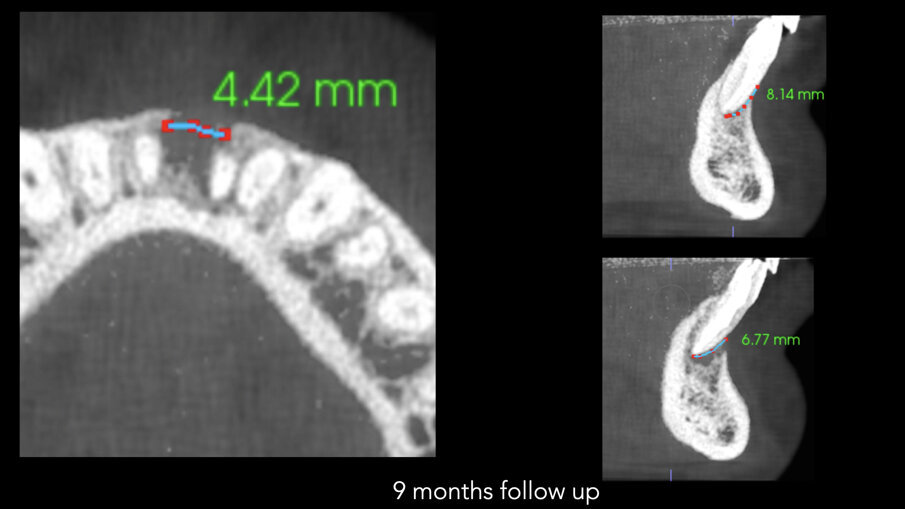

Slike 6a–c: Horizontalni pogled na i-CAT skeniranje snimljeno na kontroli nakon devet meseci koja pokazuje defekt kosti od samo 4,42 mm (a). Vertikalni pogledi na oba centralna sekutića pokazuju zarastanje kosti ispod vrhova i kost koja raste vertikalno na bukalnom aspektu (b & c)

Nedelju dana posle operacije, šavovi su uklonjeni i postavljen je finalni ispuni u obe pristupne šupljine centralnih sekutića. Urađena je radiografija neposredno nakon operacije, kao i snimak nakon devet meseci od intervencije. Poređenje snimaka pokazalo je apoziciju kosti između dva centralna sekutića (slika 4). I-CAT skeniranje je takođe napravljeno u devetomesečnom period praćenja kako bi se proverio rast kostiju. Horizontalni pogled, uzet na istom nivou kao i preoperativno, jasno je pokazao smanjenje zazora sa 14,11 mm na 4,42 mm. Isti trend u lečenju (slika 5) pokazao je vertikalni pogled -kost na bukalnoj ploči je rasla prema korenu vertikalno (slika 6) skoro 8,2 mm visine tako da je kost bila vraćena i u direktnom je kontaktu sa korenovima zuba. Zaista, kada se obezbedi „skela“ na kojoj može da raste, kost može rasti u svim pravcima, uključujući i vertikalno, gde je postojao otvoreni parodontalni džep.